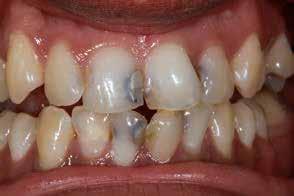

Hagyományos teljes fogsor hatékony átalakítása

Klinikánkon egy teljesen fogatlan, hagyományos akrilát fogpótlással helyreállított 65 éves férfi beteg jelentkezett, aki nem kielégítő alsó fogsorretencióra és az azzal járó problémákra panaszkodott, beleértve a kifejezetten az alsó fogsorához kapcsolódó gyenge beszéd és rágásfunkciót. A klinikai vizsgálat gömbölyűtől a késhegyig terjedő mandibulagerinc formát és megfelelő vertikális, de nem megfelelő vízszintes csontmennyiséget állapított meg, különösen a hátsó területen (1. ábra) 10